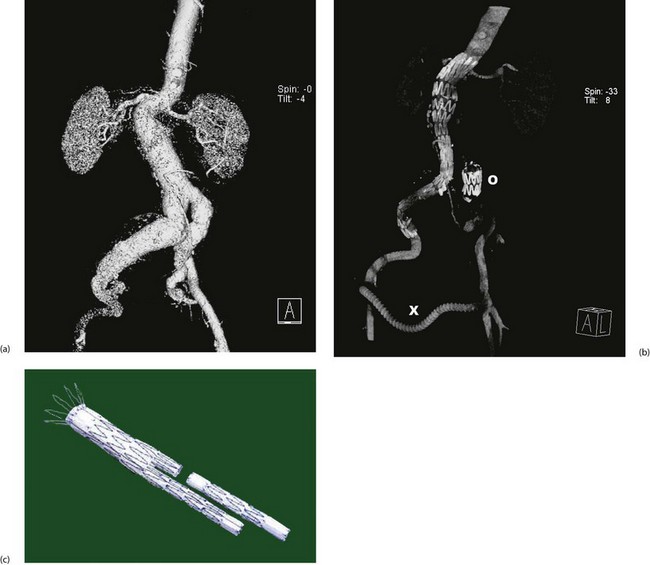

Fig. 42.5 Endovascular aneurysm repair

(a) Pre-procedure CT scan showing lumen of aorto-iliac aneurysm, suprarenal aorta and kidneys. On this view, the much larger diameter of the aneurysmal aortic wall is not visible.

(b) Post-procedure CT scan showing the stent-graft in position extending from the right common iliac to just above the renal arteries. In this case, there were technical problems placing a bifurcation graft and so the left common iliac origin was deliberately blocked with an occluding stent O and the left lower limb was revascularised with a crossover femoro-femoral graft X.

(c) Typical two-piece stent graft. Note the body and one limb are in one piece and the other limb is fitted afterwards. Note also the retaining wires at the proximal end